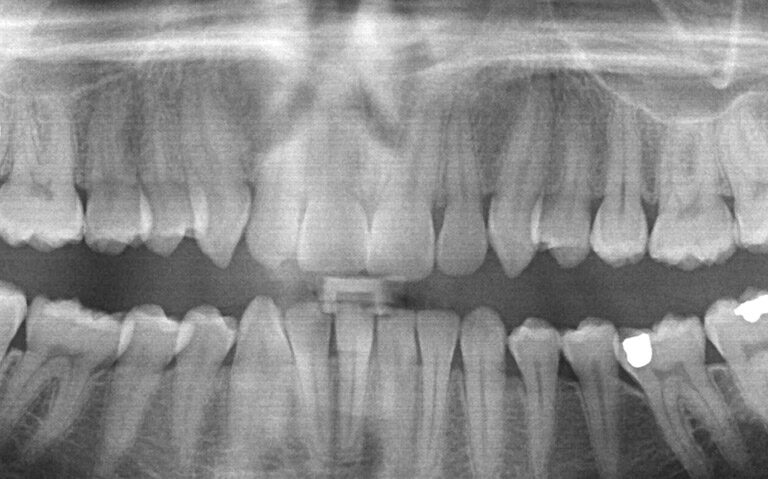

Oralna kirurgija bavi se patologijom i rekonstrukcijom čeljusnih kostiju, zuba i mekih tkiva usne šupljine. Vršimo sve oralno – kirurške zahvate od čega su najčešći: kirurško uklanjanje umnjaka i zaostalih korijenova, apikotomija, augumentacije sinusa i alveolarnih nastavaka čeljusti u sklopu dentalne implantologije te zahvati na mekim tkivima usne šupljine.

Kirurški zahvati u usnoj šupljini ili na čeljusti rješenje su za brojne tegobe. Snažna bol, oticanje, upale, anomalije i defekti samo su neke od situacija u kojima je najbolje rješenje oralna kirurgija (međuostalim; operacija zuba), a odluku za zahvat olakšat će uputa stomatologa na temelju dijagnostike.